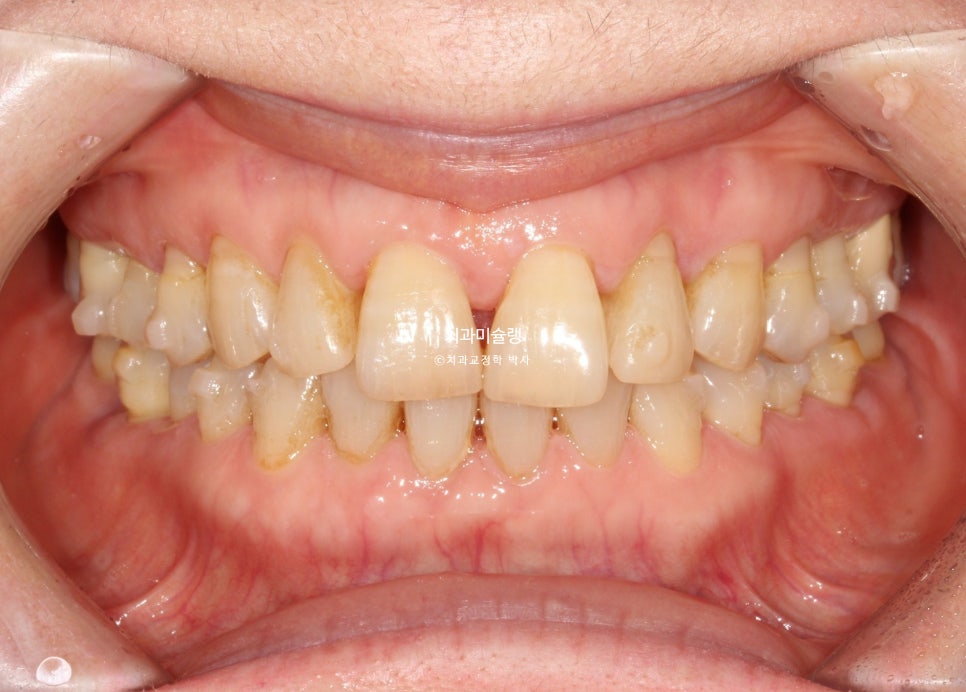

작년 2월, 앞니 틈을 교정으로 메울 방법이 있는지 상담받으러 오신 60대 환자분 입니다.

그동안 앞니가 점점 벌어지고 내려와 틈을 레진으로 메꾸고 살았는데, 레진이 자꾸 떨어지기도 하고 또 틈이 점점 더 벌어져서 교정을 알아보러 오셨죠.

앞니 사이 블랙트라이앵글이 여기저기 보입니다.

측면 사진에서 앞니 사이의 벌어진 큰 틈이 잘 보입니다.

앞니들이 벌어진것 뿐만 아니라 회전된, 소위 “나비치아”입니다.

그에비해 아래앞니는 틈도 없고 틀어짐도 경미하죠.

어금니는 배열이나 교합상 문제가 없습니다.